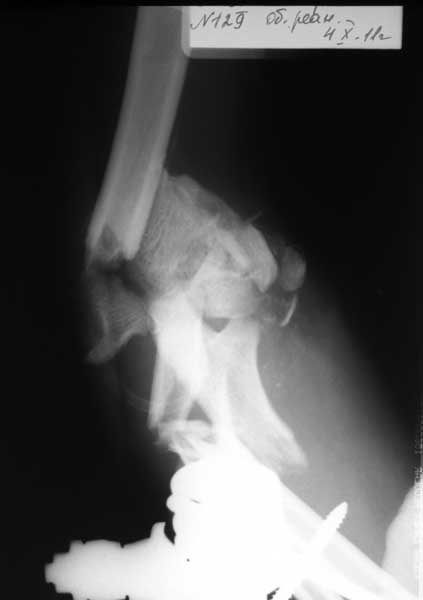

Выкладываю изображения.

План лечения: открытая репозиция. Собрать суставные фрагмент. Фиксация: спицы, кан.шурупы, реконструктивные пластины, АВФ с локтевым шарниром. Бусы с ванкомицином. Дренирование, вакууимирование.

Ориентировочно - среда.

2. КТ локтевого сустава с 3D реконструкцией. Надо определиться и понять, что осталось от дистального метаэпифиза плечевой кости, - от этого будет зависеть и дальнейшая тактика. Здесь теорию прекращаем и ждем результатов КТ.